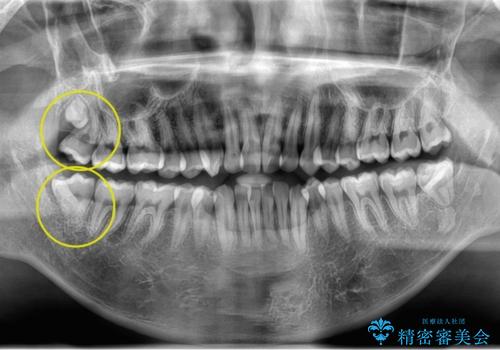

奥の虫歯 ジルコニアクラウンでの修復

左奥歯が痛い。(親知らず抜歯 ジルコニアクラウン)